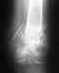

Добр время суток! был мелкооскольчатый перелом правой бедрен кости со смещением, была проведена операция с наложением пластины и винтов 17.08.2010г.разрешили наступать в марте 2010г. до сих пор проблема в контрактуре колен сустава.В данный момент сгибаю до 90 град.ходила на парафин массаж лфк сейчас хожу к массажисту-травматологу очень болезненна разработка проходит колена и процесс сгибания оччччень медленный (((. есть ли шанс разработать до конца и какие методы есть еще другие? и слегка похрамываю может стоит всетаки убрать пластину и винты,хотя оперирующий врач рекомендует не убирать.т.к гов что перелом был сложный и тебе еще надо рожать!!!!Как быть мне?Спасибо заранее )))